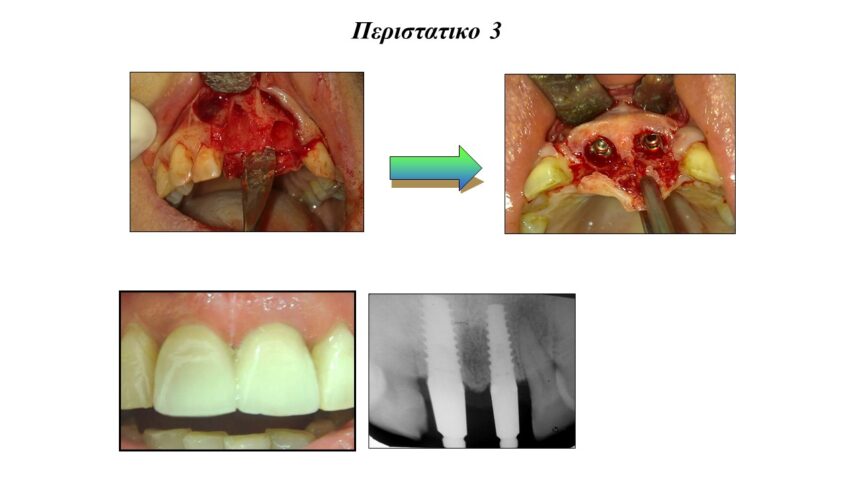

Άμεσα εμφυτεύματα και τεχνικές ώστε να αποφευχθεί η μακροχρόνια απορρόφηση της ακρολοφίας.

Τρισδιάστατη οστική ανάπλαση της ακρολοφίας με χρήση απορροφήσιμων , μη απορροφήσιμων μεμβρανών και μοσχευμάτων. Ενδείξεις, αντεδείξεις, πλεονεκτήματα - μειονεκτήματα.

Μεταξύ των επεμβάσεων - εφόσον υπάρχει χρόνος - θα παρουσιαστούν περιστατικά, ολοκληρωμένα από 20ετίας, τα οποία θα περιλαμβάνουν όλα τα παραπάνω ( τη χρήση μεμβρανών, PRF και ανύψωση της μεμβράνης ιγμορίου.